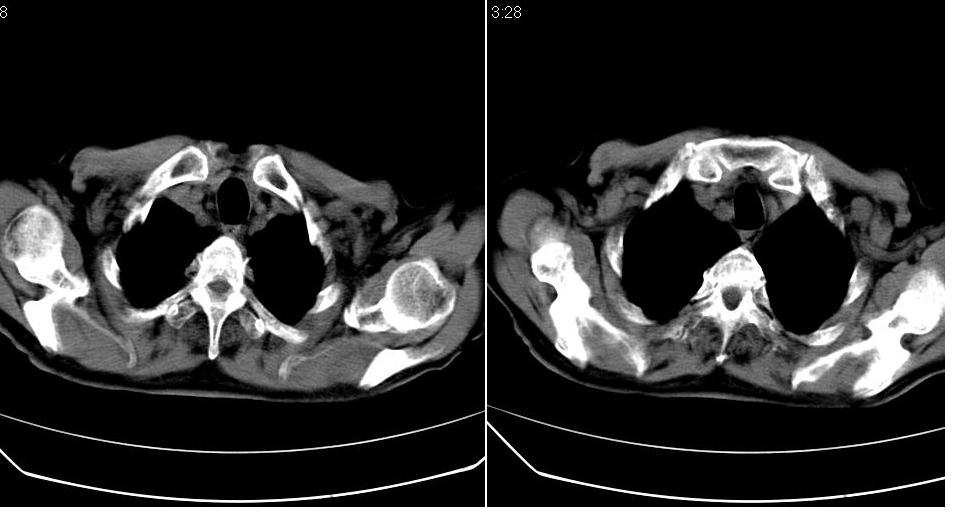

男 80岁,外院病人,有脑梗塞病史,近两个月发热,体温38.5度左右,抗炎后体温正常,药物停有发热。

左肺下叶略萎陷、实变,内可见含气支气管征。左舌叶、中叶亦见少许斑片状高密度区,边界不清。纵隔未见肿大淋巴结影。